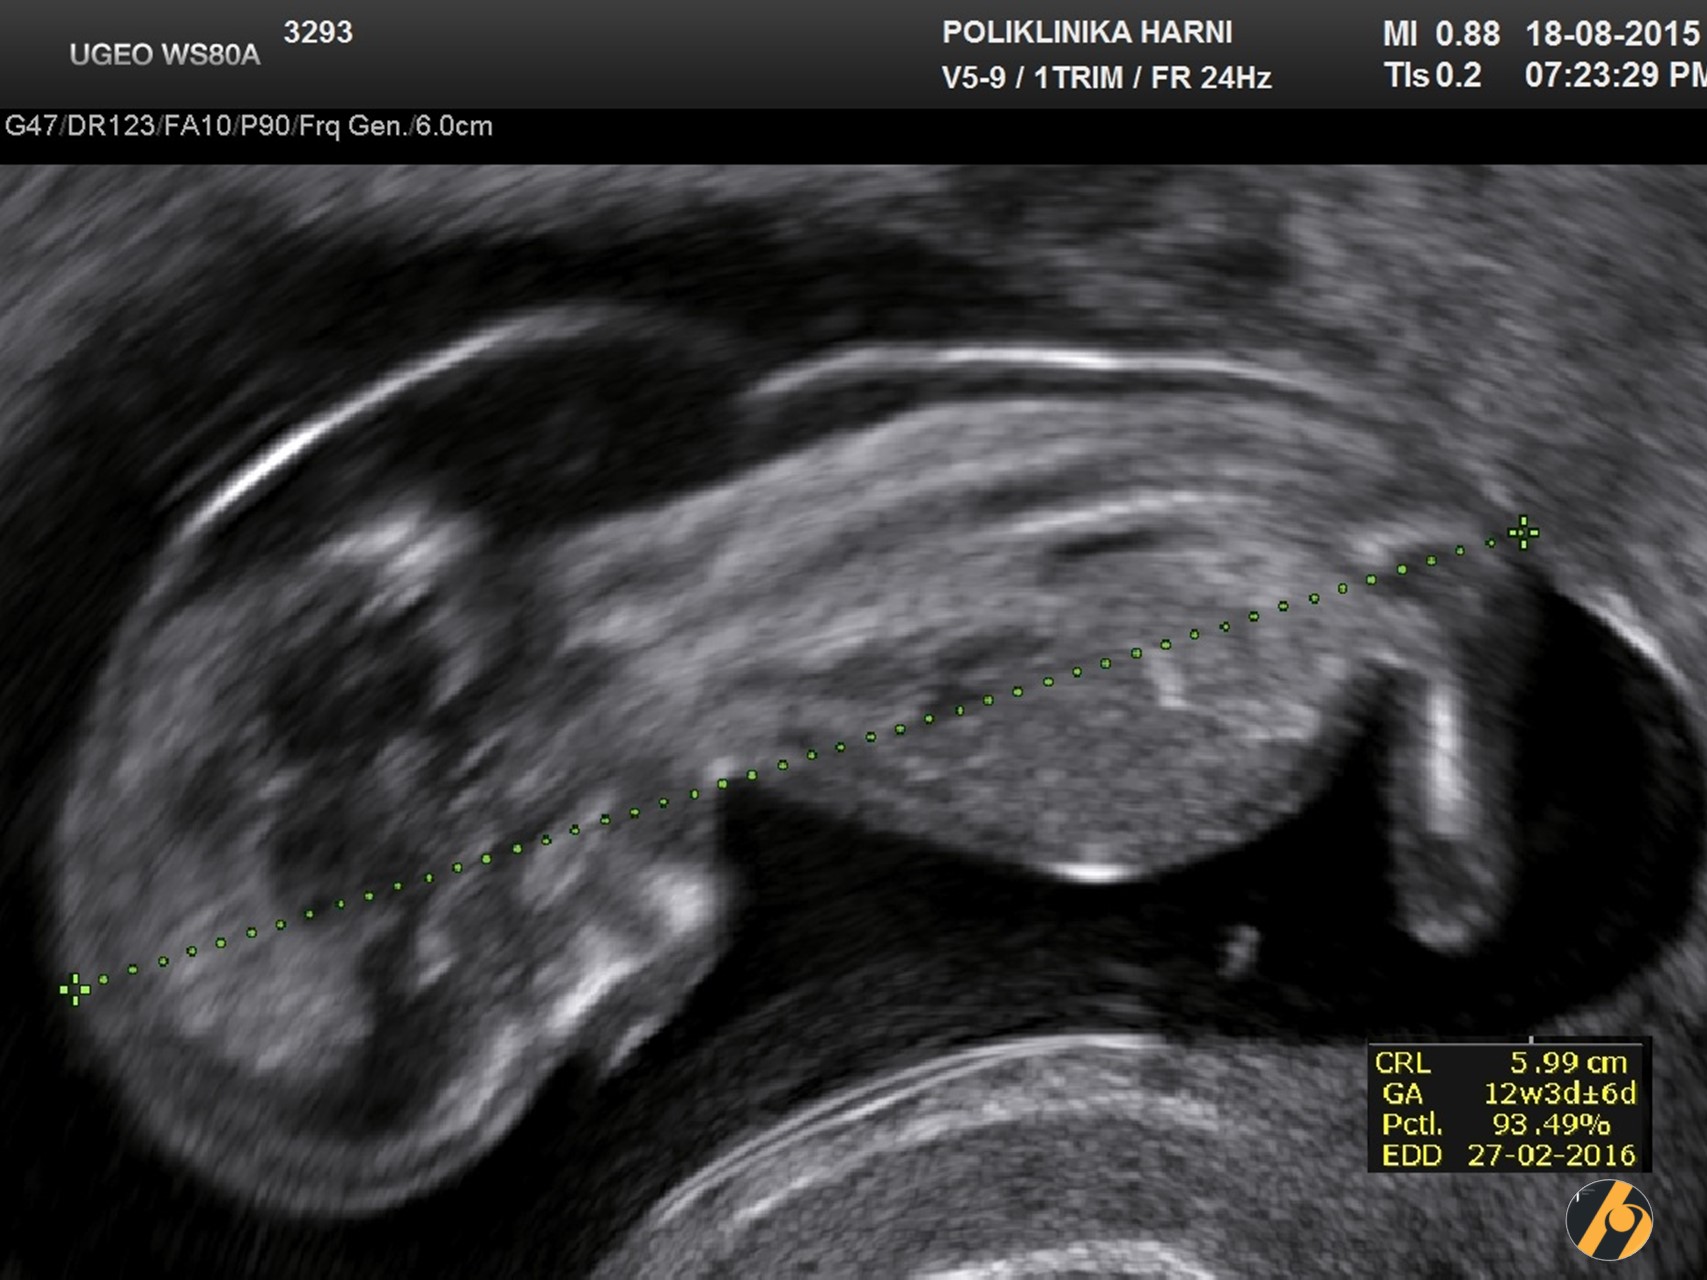

SLIKE: dr. Vesna Harni / Poliklinika Harni